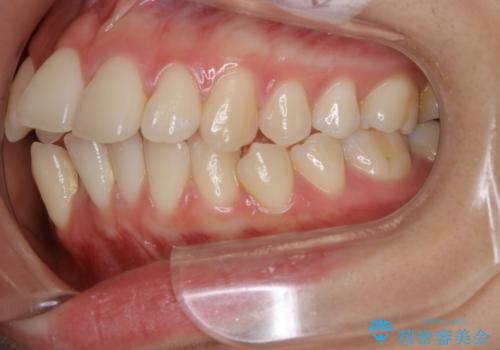

非抜歯でも劇的変化 インビザライン矯正治療

- 前歯のガタつきと噛み合わせの改善を主訴に初診来院され、審査の結果マウスピース装置による非抜歯での矯正を行うこととなりました。

元々の顎骨や口腔・歯槽骨が小さく、どうしても歯が並びきらない状況になっていました。マイクロインプラントという固定源からゴムかけを行うなど、補助装置を活用しながら臼歯部を順番に遠心方向(奥)に移動させていくことで抜歯をしなくても歯が並ぶよう計画を立てました。

歯のガタつきを治すため矯正治療を希望。審査の結果、非抜歯での矯正が可能であるという見通しが立ったためインビザラインによる非抜歯矯正治療を行った。

歯を並べるスペースを作るために、歯の遠心移動と歯列の拡大、歯自体を少しだけ小さく削る(IPR)という方法を複合的に組み合わせて配列を行いました。遠心移動用のゴムかけにはマイクロインプラントという小さいネジを用いて骨に直接固定源を求めました。